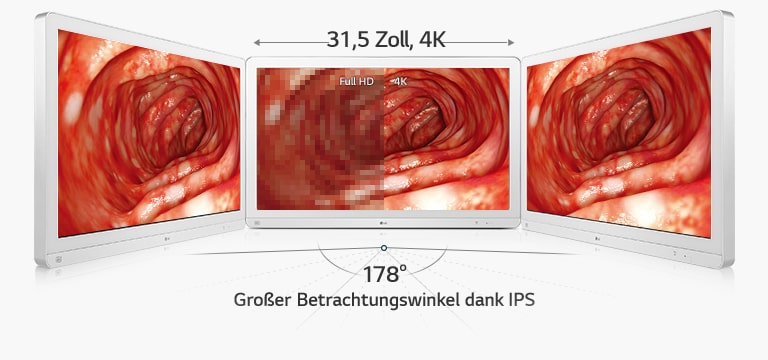

Der OP-Monitor 32HL714S unterstützt 115% sRGB (Farbraum) und über 99% sRGB (Farbabdeckung) sowie den Standard DICOM Part 14 und wurde für eine genaue Farberkennung und Tiefenwahrnehmung während chirurgischer Eingriffe entwickelt. So können Chirurgen genaue, realitätsgetreue Bilder betrachten und Operationen präzise durchführen.